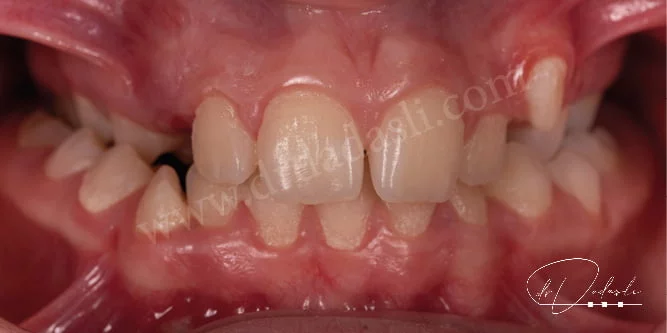

- Çapraşıklık (Şekil 10) – dişlerle çene arasında boyut uyumsuzluklarından dolayı, dişler çenelere sığamazlar ve çapraşıklık oluşur.